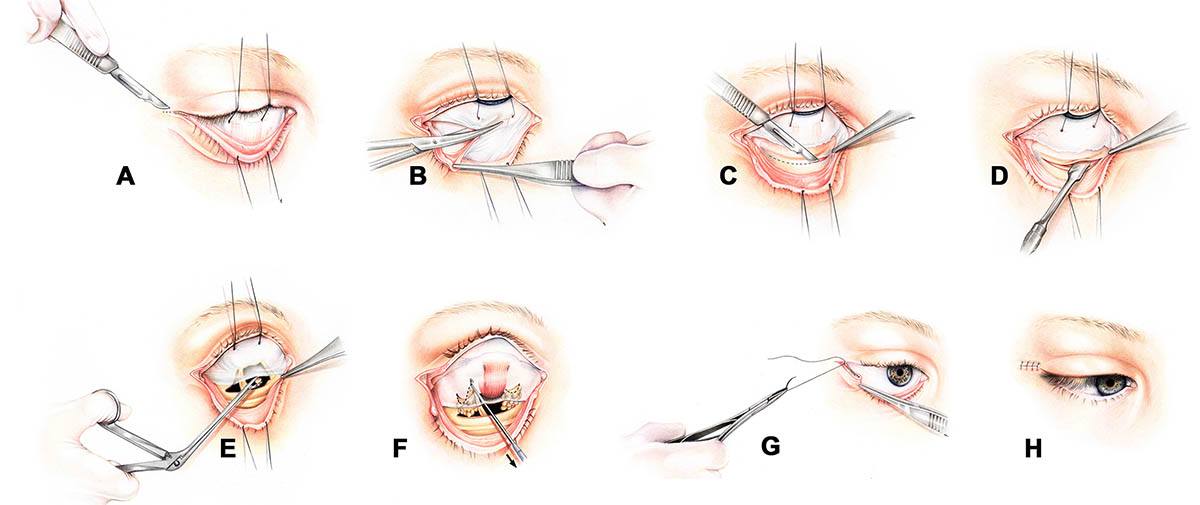

Surgical correction with orbital decompression

Once the inflammatory phase has stabilized, orbital decompression surgery can restore the natural position of the eyes. During this operation, small sections of orbital bone and, when needed, excess orbital fat are removed to relieve pressure and create space within the orbit. The eye then settles backward into a more normal alignment, improving both function and appearance.

He specializes in the transconjunctival (swinging-eyelid) approach, which allows access to the orbit through the inside of the eyelid—leaving no external scars. This minimally invasive technique provides excellent visualization of the orbital walls, precise bone removal, and controlled decompression, while preserving critical support structures to minimize the risk of postoperative double vision.